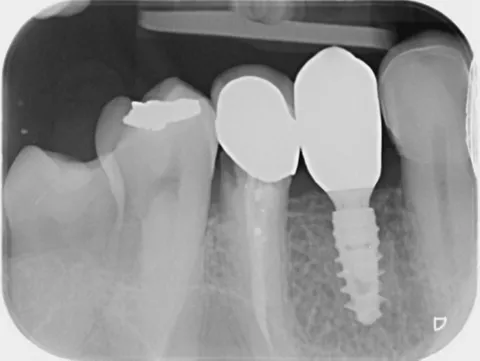

17a. 17b. Periapical radiograph of the implant at tooth position (LL5 LL4 and UL4 and), obtained 4 months post‑implantation

17a

17b